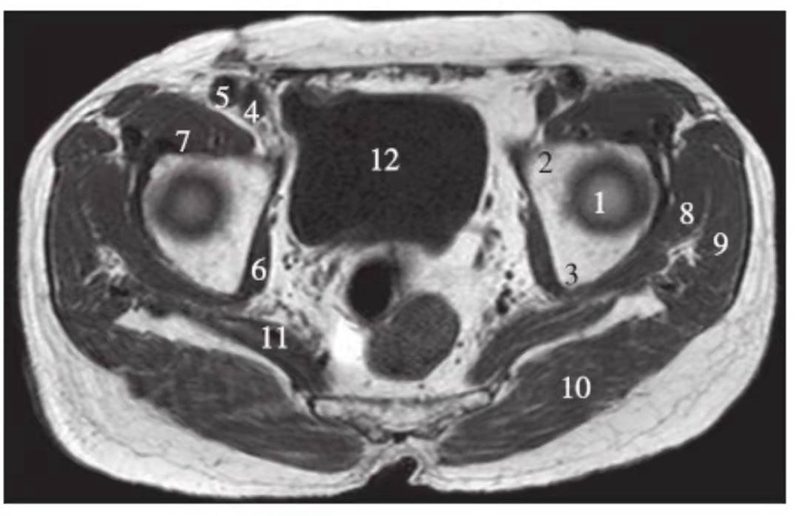

横轴位

正常髋关节股骨头上缘层面T1WI像

1.股骨头;2.耻骨;3.坐骨;4.股静脉;5.股动脉;6.闭孔内肌;7.髂腰肌;8.臀小肌;9.臀中肌;10.臀大肌;11.梨状肌;12.膀胱